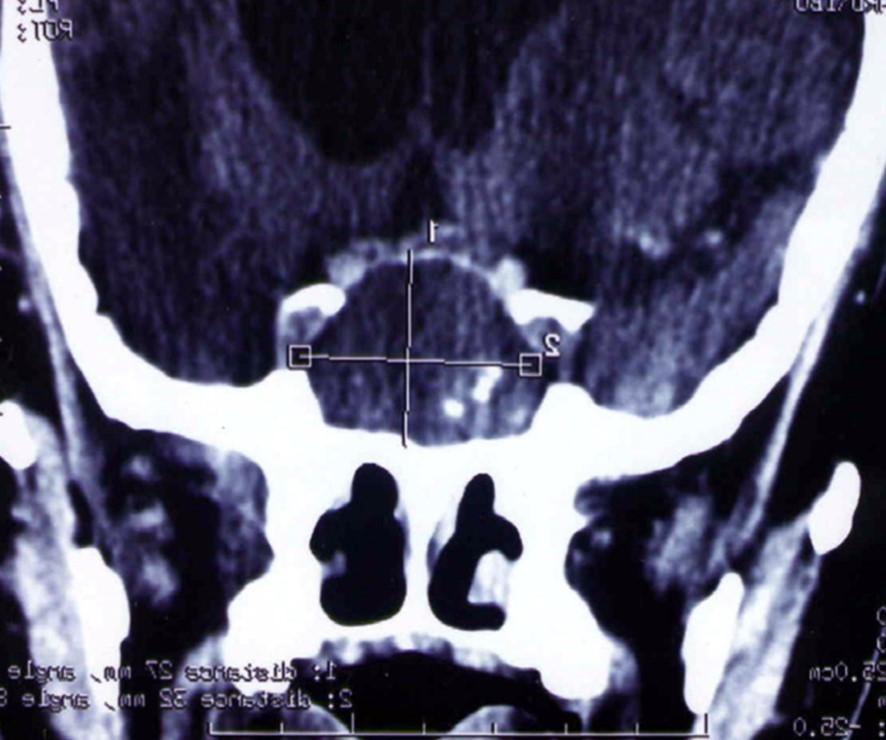

A 65 year-old man presented with progressive visual decrease and ptosis in the left eye. Neurological examination revealed paresis of the 3rd left cranial nerve. Fundoscopy revealed bilateral papillary paleness and visual acuity was: 4/10 at left; 7/10 at right. No signs of endocrine insufficiency or hypersecretion were assessed. There was no evidence of sinusitis. Chest X-ray, routine laboratory investigations and hormonal blood tests were normal. A CT scan showed a hypodense mass enlarging the sphenoid sinus and sellar region with calcification like images and bone erosion of the sellar floor (Figure 5). MRI showed a mass of 26 mm x 33 mm x 25 mm in the sphenoidal sinus ans sellar region, with hypersignal intensity in T1-weighted (Figure 6A) ans T2-weighted sequences, and hyposignal zone in T2-weighted sequences (Figure 6B). Imaging investigations were suggestive of unusual pituitary macroadenoma. The patient underwent a transnasal transsphenoidal approach for excision of the mass. A yellow-brownish gluey material with gummy debris was aspirated from the sphenoid sinus, which was completely cleaned. The sellar floor was eroded which allowed a view of the intact inflammatory dura. An intra-operative presumptive diagnosis was made of caseating granuloma (i.e tuberculosis). The post-operative course was uneventful: the patient recovered from ptosis and visual acuity improve at discharge. Mycobacterium tuberculosis could not be cultured from specimens; and cultures on Sabouraud’s medium did not isolate Aspergillus. Pathologic findings were of non invasive aspergillosis, with many septated fungal hyphae being present without tissue invasion. The patient was not given antifungal drugs because the intrasphenoidal material was completely aspirated. At 6 month and 18 months follow up, the patient had no neurological complaint. No recurrence was observed on control CT scans.

Figure 5.CT scan showing a hypodense mass enlarging the sphenoid sinus and sellar region with calcification like images and bone erosion of the sellar floor